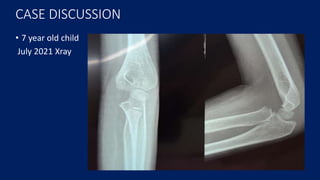

CASE DISCUSSION

• 7 year old child

July 2021 Xray